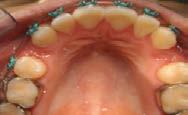

La alineación y nivelación fue iniciada con arcos NiTi .012 (Figura 5).

Tomando en cuenta un adecuado diagnóstico por las características estéticas, edad y tipo de maloclusión se realizaron extracciones de los 4 primeros premolares; y se comenzó con el uso de brackets MBT slot 0.022x28 en abril 2014.

En diciembre de 2014, en la cita 16 para continuar con la mecánica de cierre de espacios, fueron colocados arcos de cierre 19 x 25 de acero preposteados U/L, los cuales se decide cerrar en retracción (C) (Figura 7).

En mayo de 2016 se realizó el ajuste 33 y se colocó en la arcada inferior 19X25L para tener mayor control de tipping y torque, y en la arcada superior se colocó una cadena de 6-6 para

cerrar los diastemas y tremas pequeños y así conformar y consolidar las arcadas superiores (Figura 8).

En junio de 2016 se realiza ajuste 34 Rep UR2 14X25U, entorchado 6-6 L, resinas en UL3, UR3, LL3, LR3 (Figura 9).

La paciente concluyó su tratamiento en diciembre de 2016, el tratamiento activo duró 3 años. La retención elegida fue un circunferencial en superior e inferior un fijo de premolar a premolar.